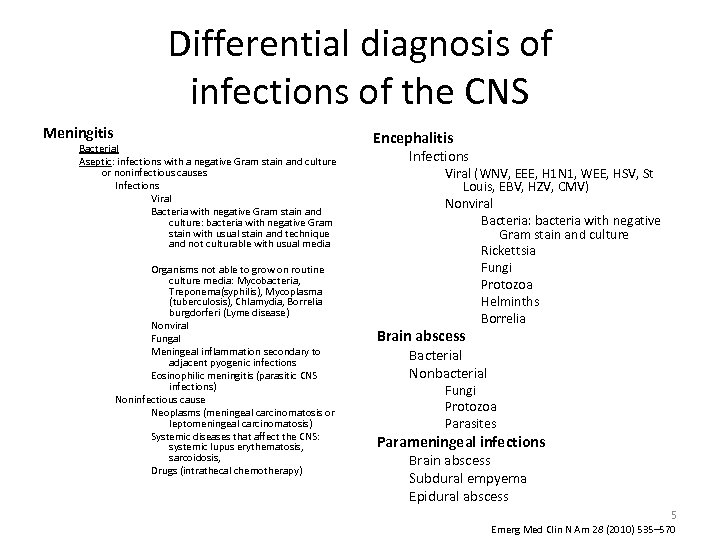

Differential diagnosis of infections of the CNS Meningitis Bacterial Aseptic: infections with a negative Gram stain and culture or noninfectious causes Infections Viral Bacteria with negative Gram stain and culture: bacteria with negative Gram stain with usual stain and technique and not culturable with usual media Organisms not able to grow on routine culture media: Mycobacteria, Treponema(syphilis), Mycoplasma (tuberculosis), Chlamydia, Borrelia burgdorferi (Lyme disease) Nonviral Fungal Meningeal inflammation secondary to adjacent pyogenic infections Eosinophilic meningitis (parasitic CNS infections) Noninfectious cause Neoplasms (meningeal carcinomatosis or leptomeningeal carcinomatosis) Systemic diseases that affect the CNS: systemic lupus erythematosis, sarcoidosis, Drugs (intrathecal chemotherapy) Encephalitis Infections Viral (WNV, EEE, H 1 N 1, WEE, HSV, St Louis, EBV, HZV, CMV) Nonviral Bacteria: bacteria with negative Gram stain and culture Rickettsia Fungi Protozoa Helminths Borrelia Brain abscess Bacterial Nonbacterial Fungi Protozoa Parasites Parameningeal infections Brain abscess Subdural empyema Epidural abscess 5 Emerg Med Clin N Am 28 (2010) 535– 570